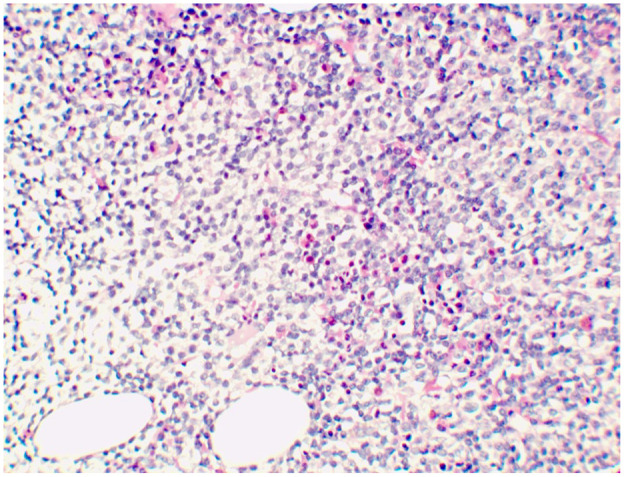

急性肾损伤(AKI)在非霍奇金淋巴瘤有多种病因。我们报告一例由轻链铸型肾病引起的AKI是结外边缘区淋巴瘤的初始表现,没有全身性症状。一名64岁男性,表现为严重AKI,无其他症状。体格检查及肾脏超声检查无明显异常。肾活检显示轻链铸型肾病,随后骨髓活检证实边缘区淋巴瘤。患者接受R-CHOP化疗(利妥昔单抗、环磷酰胺、阿霉素、长春新碱、强的松龙)共6个周期。病人对淋巴瘤有部分反应。然而,他的肾功能没有改善,最终发展为终末期肾病,需要维持血液透析。本病例强调结外边缘区淋巴瘤表现为AKI,强调其在没有全身性症状的情况下独特的肾脏局限性表现,以及肾活检在诊断不明原因AKI中的关键作用。

Acute kidney injury (AKI) in non-Hodgkin lymphoma has diverse etiologies. We report a case in which AKI due to light chain cast nephropathy was the initial manifestation of extranodal marginal zone lymphoma, occurring without systemic symptoms. A 64-year-old male presented with severe AKI without other symptoms. His physical examination and renal ultrasound were unremarkable. Renal biopsy revealed light chain cast nephropathy, and a subsequent bone marrow biopsy confirmed marginal zone lymphoma. The patient received R-CHOP chemotherapy (rituximab, cyclophosphamide, doxorubicin, vincristine, and prednisolone) for a total of six cycles. The patient had a partial response to lymphoma. However, his renal function did not improve, and ultimately he progressed to end-stage kidney disease, requiring maintenance hemodialysis. This case highlights extranodal marginal zone lymphoma presenting as AKI, emphasizing its unique renal-limited manifestation in the absence of systemic symptoms and the critical role of renal biopsy in diagnosing unexplained AKI.